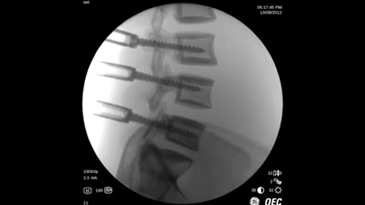

Brivo OEC 785 - это надёжная С-дуга, которая работает вместе с вами, эффективно устраняя сложности визуализации и позволяя хирургу сфокусироваться на пациенте. Отличительной чертой системы Brivo OEC 785 является высокое качество визуализации, на которое можно рассчитывать изо дня в день. Вы можете доверить технологиям GE Healthcare точное и эффективное получение чётких изображений, даже при низкой дозе. Автоматизированные смарт-функции Brivo OEC созданы, чтобы вы получали изображения высокого качества, даже в клинически сложных случаях. Подобно тому, как орлиный глаз может различить движение и малозаметные объекты, эта система делает упор на получение изображения высокой точности при любой степени клинической сложности.

- Четкая визуализация и клиническая надежность

Получение четких изображений с помощью «умной» цепи визуализации. - Удобная работа